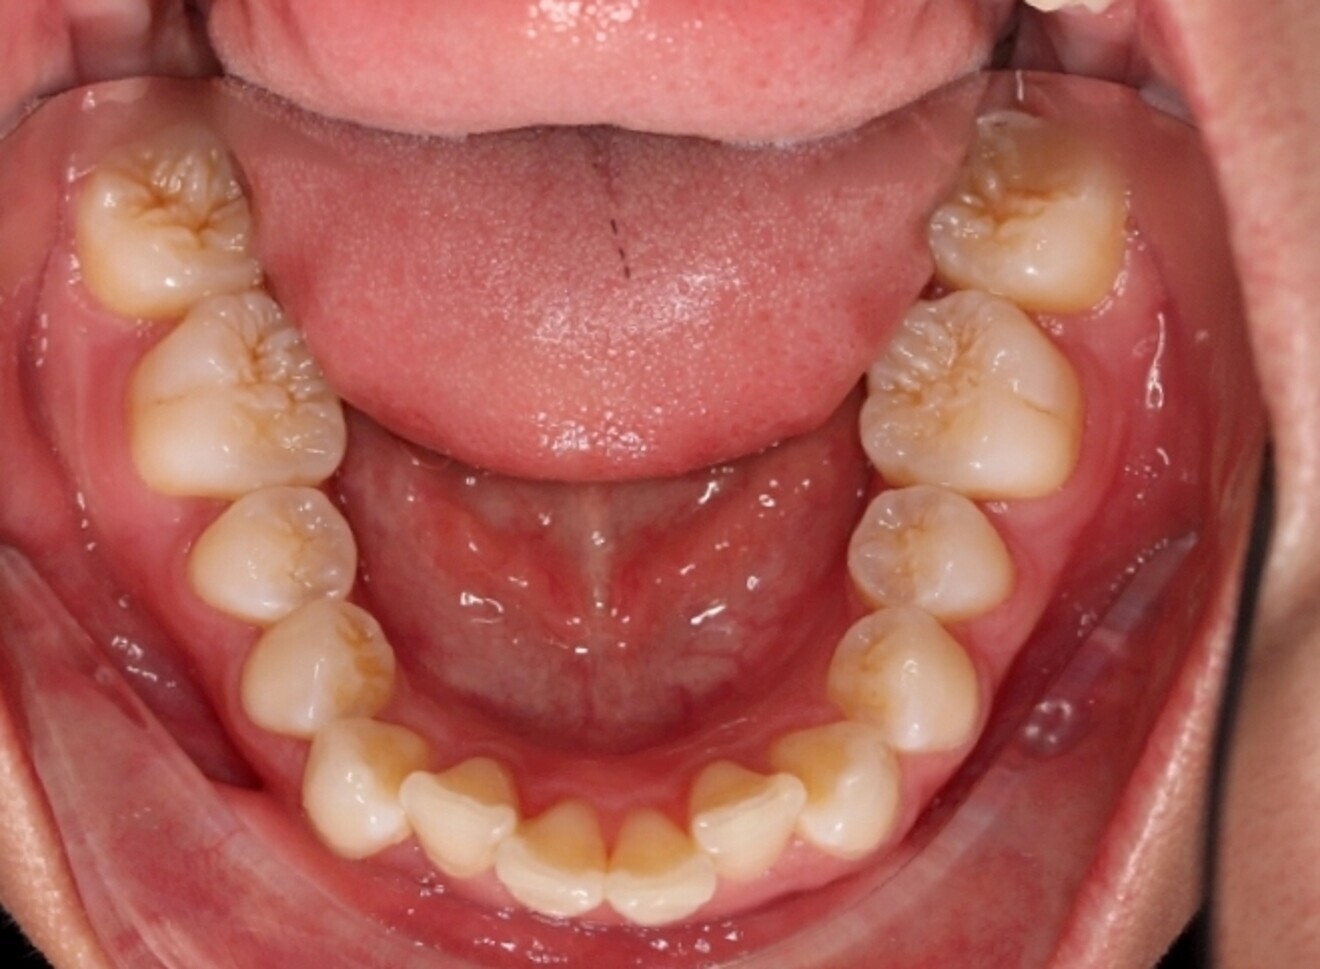

The starting point for Oratomic4D was selecting a real patient to replicate. After an extensive search, the patient, Tina, was chosen for her ideal oral anatomy and range of treatments that could be simulated. Unlike a typodont model, Tina had mild crowding, impacted maxillary and mandibular third molars, and complex root canal anatomy (Figs. 2–7).

These irregularities in Tina’s oral anatomy made her an ideal candidate for the creation of a range of realistic simulation models that are highly representative of the types of patients encountered in dental practice.